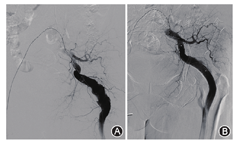

患者女,69岁,因"发现左臀部搏动性肿块1年"住院治疗,自诉有数年活动后下肢不适症状。查体:左臀部扪及搏动性包块,大小约5 cm×5 cm,轻压痛,左侧股动脉搏动弱,腘动脉搏动尚可,足背动脉未及,右侧正常。下肢CT血管造影(CTA)见髂内动脉发出粗大分支至左下肢,伴瘤样扩张,同侧股动脉纤细(图1)。术前诊断为永存坐骨动脉合并坐骨动脉瘤形成。于局麻下行下肢动脉造影,测量瘤体长度95 mm,近端直径13 mm,远端直径11 mm(图2A),遂选用戈尔公司viabahn支架13 mm×13 mm×100 mm一枚及美敦力公司Endurant支架16 mm×16 mm×93 mm一枚,支架重叠约5 cm,术后瘤体不显影,无内漏(图2B)。术后左臀部搏动性肿物消失,疼痛症状明显好转。术后随访至29个月,CTA复查支架无狭窄、无变形,下肢血流通畅(图3A)。后患者自行停用抗血小板药物,随访至术后46个月,支架完全闭塞(图3B),但患者未诉下肢缺血症状,决定继续随访观察。

注:A图:术中造影示坐骨动脉瘤;B图:术毕造影示支架形态良好,无内漏